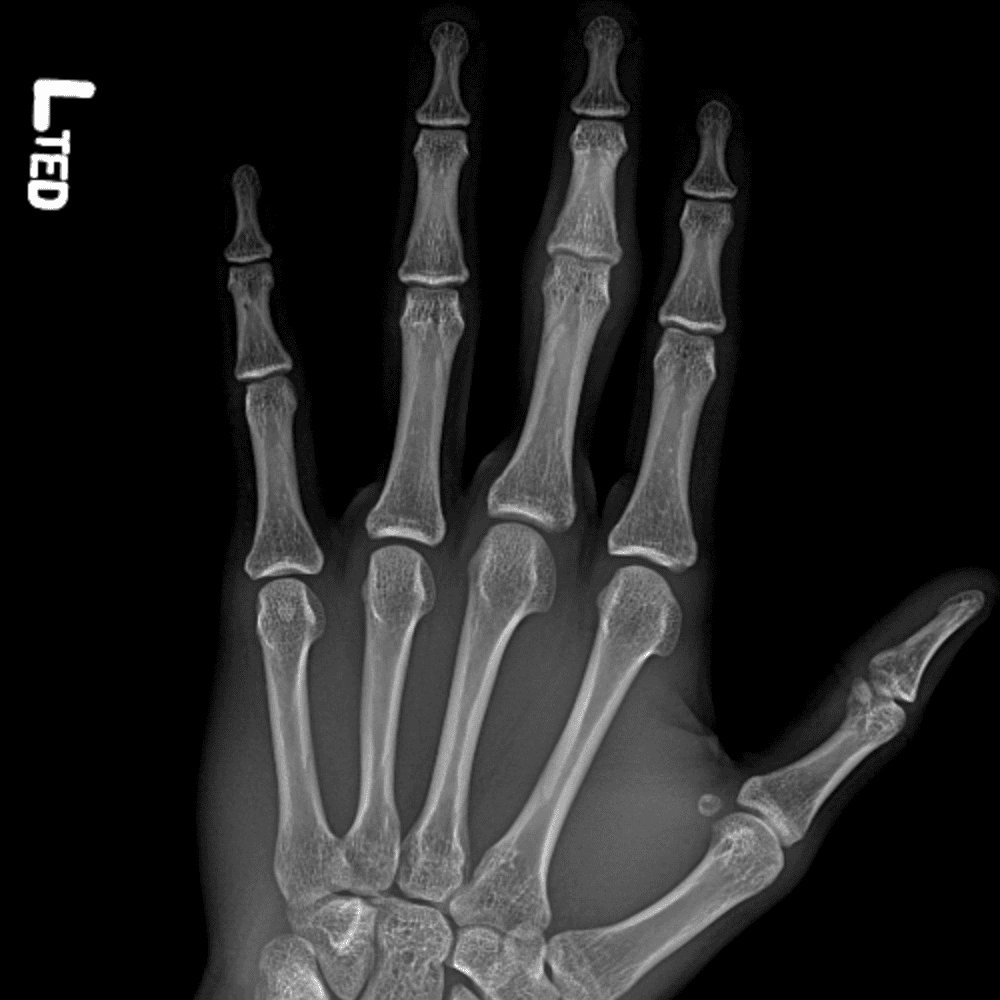

Simulates call by including subtle or difficult cases and some normals.

30 cases